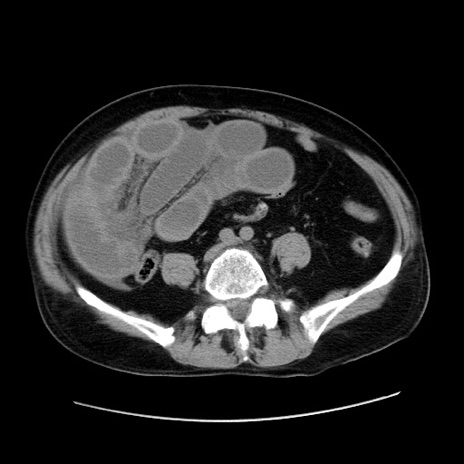

症例30(横断像)

【症例】80歳代男性

【主訴】臍周囲痛

【現病歴】約6時間前から臍下部痛が出現。次第に腹部膨隆・背部痛も生じてきたため来院。背部痛の場所は変化しない。

【身体所見】意識清明、BT 36.3℃、BP  131/87mmHg、P 87bpm、SpO2 100%(RA)、臍周囲自発痛・圧痛あり、反跳痛なし、自発痛部位に一致して板状硬あり、腹部膨隆、腸雑音減弱、CVA tenderness両側陰性。

【データ】WBC 19600、CRP 0.33